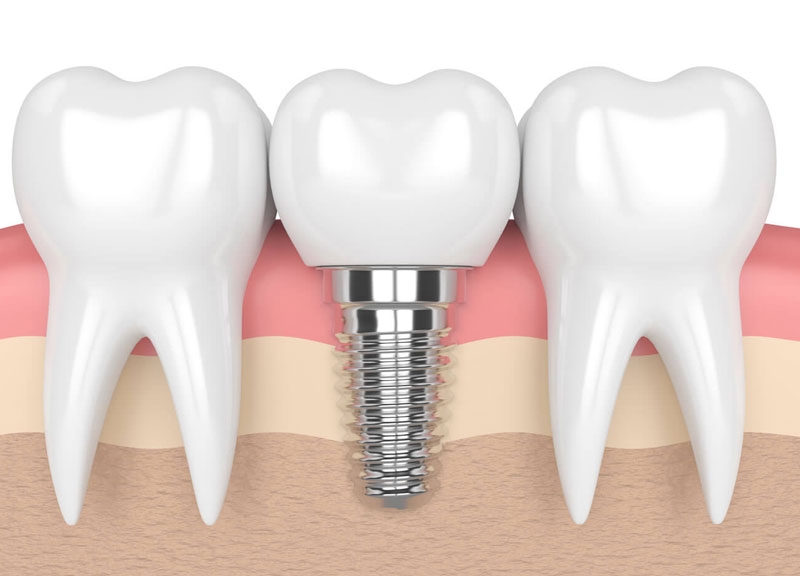

Implant nha khoa là gì?

Trồng răng Implant là phương pháp phục hồi răng mất hiện đại, trong đó bác sĩ sẽ cấy một trụ titanium vào trong xương hàm để thay thế chân răng thật đã mất. Sau một thời gian, trụ này sẽ tích hợp chắc chắn với xương nhờ cơ chế Osseointegration, sau đó bác sĩ gắn mão sứ lên trên để hoàn thiện chiếc răng.

So với cầu răng sứ hoặc hàm tháo lắp truyền thống, trồng răng Implant mang lại nhiều ưu điểm vượt trội về độ bền, thẩm mỹ cũng như khả năng ăn nhai. Đây là lý do tại sao Implant đang dần trở thành lựa chọn hàng đầu trong phục hình răng.

Bước 2: Cấy ghép trụ Implant

Trong điều kiện vô trùng, bác sĩ đặt trụ Implant vào xương hàm bằng tiểu phẫu nhỏ. Thời gian thực hiện thường chỉ khoảng 30 – 60 phút cho một trụ.

Bước 4: Gắn răng sứ hoàn thiện

Khi trụ đã ổn định, bác sĩ tiến hành gắn Abutment (khớp nối) và mão răng sứ, hoàn thiện chức năng và thẩm mỹ của răng.